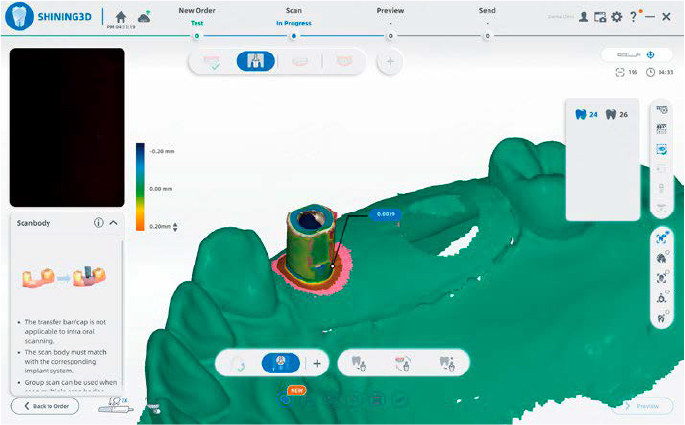

ALLINEAMENTO CON SCANBODY

Librerie integrate dei principali brand per un allineamento preciso con un solo click, riducendo i ritocchi e ottimizzando il workflow delle riabilitazioni implantari.